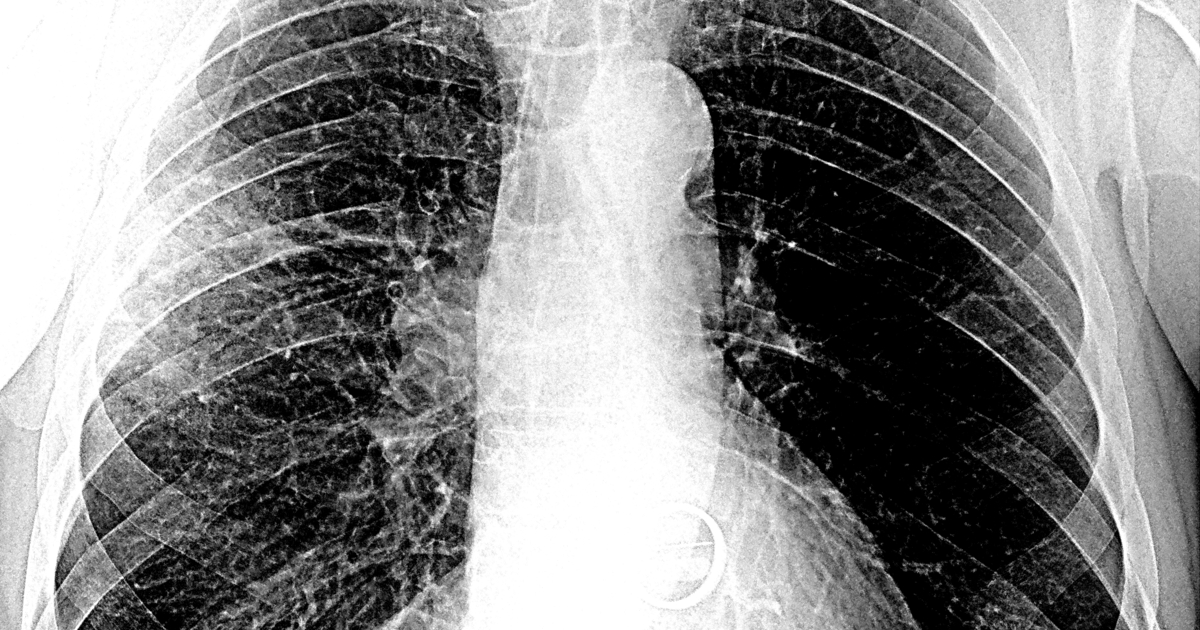

По словам эксперта, у «Омикрона» эффективные механизмы присоединения к рецепторам и проникновения в клетки человеческого организма. Поэтому он быстрее, чем другие варианты SARS-CoV-2, опускается в лёгкие, вызывая пневмонию. Если при других штаммах от момента заражения до развития пневмонии проходило 10–11 дней, сейчас этот период сократился до 3–5 дней.

При этом «Омикрон» немногим отличается от других штаммов. «Оно меняется и становится более эффективным, но мы пока всего не знаем. Тесты на нейтрализацию вируса занимают достаточно много времени, но биоинформатические исследования уже проведены во многих странах, в том числе и в России. И учёные не нашли ничего такого, что бы ставило свойства вируса с ног на голову. Что плохо в штамме «Омикрон», он точно так же, как и «Дельта», более тропен, то есть способен к взаимодействию с эпителием лёгких — нижних дыхательных путей. Поэтому «Омикрон» быстрее спускается в лёгкие, вызывая пневмонию. Это очень тревожно», — отметил Семёнов.